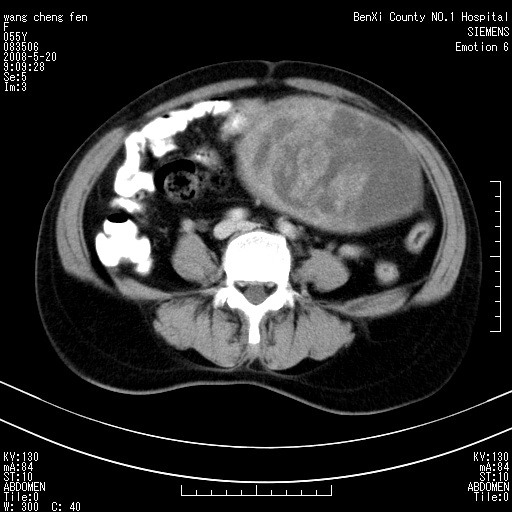

左侧附件区巨大囊实性病灶,边缘光整,病灶囊壁较厚,增强示囊壁及实性部分明显强化,强化呈度与宫体实质大致相同,宫腔积液征像,未见盆腔积液等其他异常,考虑左侧卵巢囊腺癌,不除外囊腺瘤及浆膜下肌瘤坏死

左侧附件区巨大囊实性病灶,边缘光整,病灶囊壁较厚,增强示囊壁及实性部分明显强化,强化呈度与宫体实质大致相同,宫腔积液征像,未见盆腔积液等其他异常。绝经后阴道流血3个月,结合病史左侧卵巢囊腺癌首先考虑,宫腔扩大不除外累及。期待结果。

左侧卵巢囊实性占位,结合年龄和病史,考虑卵巢囊腺癌或囊腺瘤。

囊实性肿块分隔厚度较大,厚薄不均,增强实性成分明显强化,有不规则阴道流血,卵巢囊腺癌可能性大。